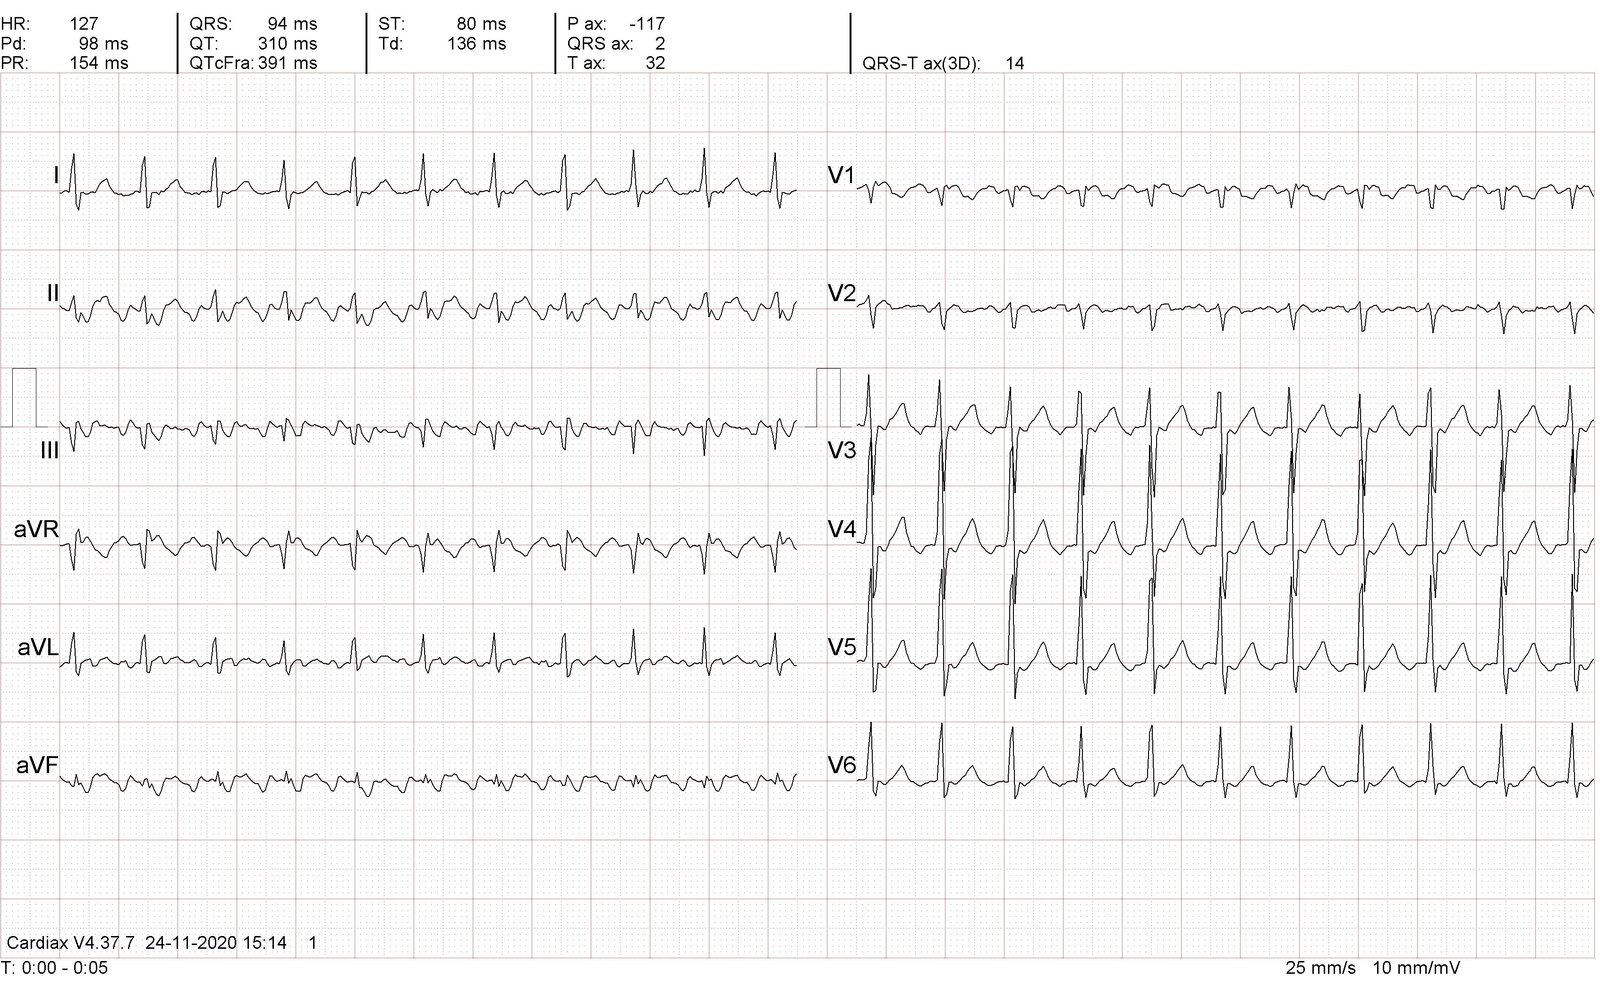

• 12-lead ECG: initial investigative study to confirm Afib

ECG findings in atrial fibrillation [13]

Appearance

Rhythm

• Irregularly irregular RR intervals

• Rarely may be regular if there is complete AV dissociation

Rate Afib with RVR

• Ventricular rate > 100–110/minute (tachycardic Afib) [14][15]

Afib with SVR (slow Afib)

• Ventricular rate < 60/minute (bradycardic Afib or slow Afib) [16]

P waves

• P waves are indiscernible.

• Fibrillatory waves (f waves) are seen instead at a frequency of 300–600/minute

• Recent-onset Afib: prominent, coarse f waves with higher amplitude in leads V1, II, III, and aVF

• Chronic Afib: f waves have low amplitudes and may appear as an undulating baseline.

• PR intervals: not distinguishable

QRS complex

• Typically narrow QRS complex (< 0.12 seconds)

• Wide QRS complex may be seen in some situations:

• Aberrant conduction, e.g., bundle branch block or preexcitation (as seen in Afib with WPW)

• Complete AV block with a ventricular escape rhythm

• Ashman phenomenon: intermittent aberrant ventricular conduction results in isolated or short runs of wide QRS complexes

Irregularly irregular NCT with a rate > 100–110/minute and no discernable P waves on ECG strongly suggests Afib with RVR.